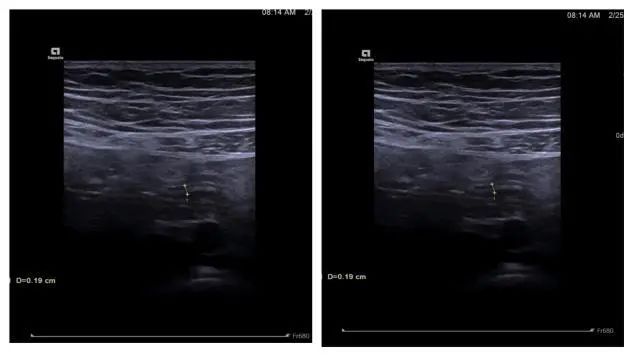

X 线确认支架位置合适,退镜结束治疗。术后小朋友自述腹痛明显缓解,术后第一天查房,小朋友腹痛消失,活动自如,感染指标下降;术后第三天复查阑尾支架位置良好,支架通畅,家属对于治疗效果非常满意。